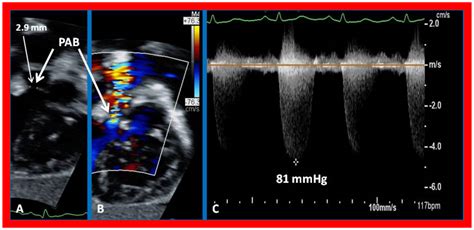

Modern advancements in pediatric cardiology have made early detection of Double Inlet Left Ventricle much more accurate. In many cases, the condition is identified during a prenatal fetal echocardiogram, allowing for a planned delivery at a specialized cardiac center. After birth, infants are monitored closely through a variety of diagnostic tools.

• double inlet lv echo